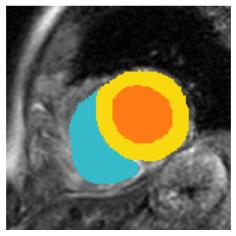

Although supervised deep-learning has achieved promising performance in medical image segmentation, many methods cannot generalize well on unseen data, limiting their real-world applicability. To address this problem, we propose a deep learning-based Bayesian framework, which jointly models image and label statistics, utilizing the domain-irrelevant contour of a medical image for segmentation. Specifically, we first decompose an image into components of contour and basis. Then, we model the expected label as a variable only related to the contour. Finally, we develop a variational Bayesian framework to infer the posterior distributions of these variables, including the contour, the basis, and the label. The framework is implemented with neural networks, thus is referred to as deep Bayesian segmentation. Results on the task of cross-sequence cardiac MRI segmentation show that our method set a new state of the art for model generalizability. Particularly, the BayeSeg model trained with LGE MRI generalized well on T2 images and outperformed other models with great margins, i.e., over 0.47 in terms of average Dice. Our code is available at https://zmiclab.github.io/projects.html.